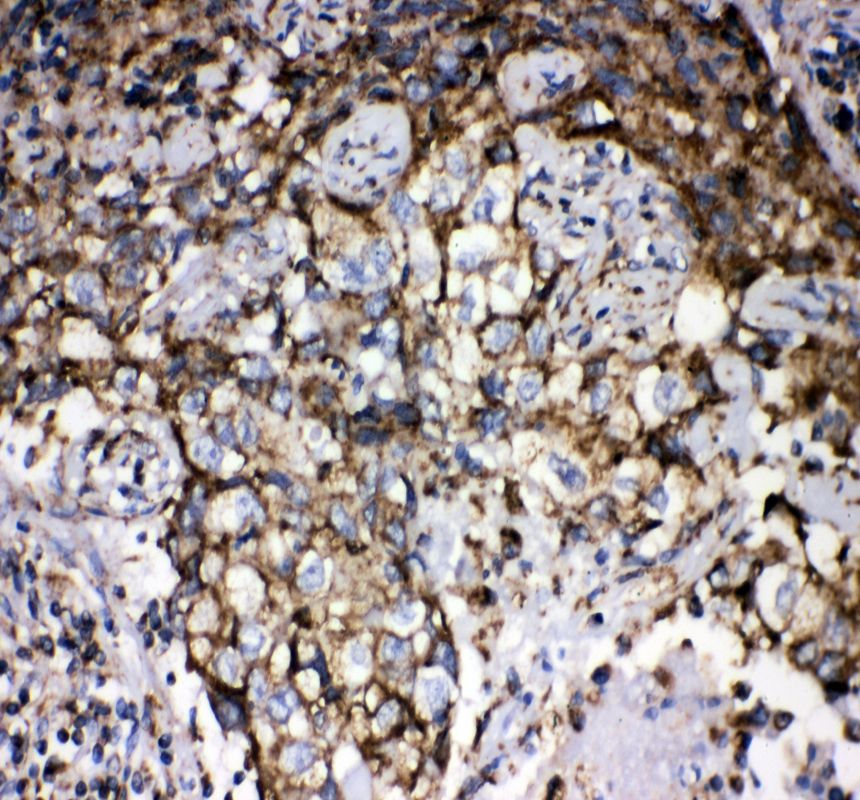

IHC analysis of GRP75/HSPA9 using anti-GRP75/HSPA9 antibody (PB0668) .

GRP75/HSPA9 was detected in a paraffin-embedded section of human lung cancer tissue. The tissue section was incubated with rabbit anti-GRP75/HSPA9 Antibody (PB0668) at a dilution of 1:200 and developed using HRP Conjugated Rabbit IgG Super Vision Assay Kit (Catalog # SV0002) with DAB (Catalog # AR1027) as the chromogen.